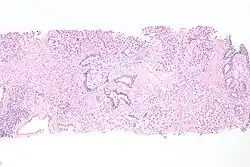

| Histopathology of transitional carcinoma of the urinary bladder. Transurethral biopsy. Hematoxylin and eosin stain. | |

Micrograph of urethral urothelial cell carcinoma. H&E stain